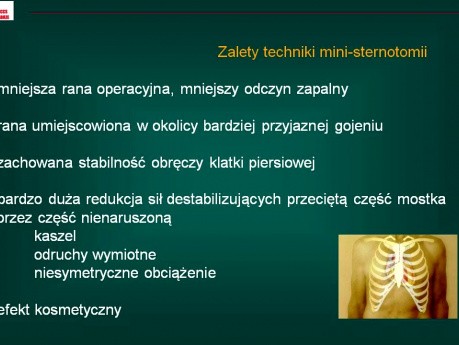

Małoinwazyjna wymiana zastawki aortalnej

Czy powinna być standardem postępowania przy izolowanej wadzie zastawki aortalnej? Tematem prezentacji jest chirurgiczna wymiana zastawki aortalnej wykonywanej z użyciem tzw. ministernotomi - częściowego...